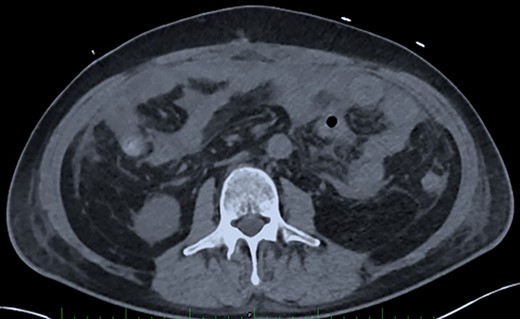

On Days 19 and 20, the patient reported no pain, with only transient febrile episodes at 38.1°C during the night. Abdominal examination was normal, and stomas, wall VAC and dressings (which were repeated daily under sedation) did not show any issues. CRP and WBC counts were stable. In contrast to the apparent clinically stable picture, PSP dosing showed elevated concentrations of 392 ng/ml and >600 ng/ml on Days 19 and 20 respectively. Based on this, a new abdominal CT-scan was performed and showed several intraperitoneal fluid collections of radiological density suggestive of an intra-abdominal infection (Fig. 3). The patient was returned to the operating room and surgery confirmed intra-abdominal infection and post-operative peritonitis with purulent collections (cultures will show E. coli 48 h later). An intraperitoneal lavage was performed, the abdomen was kept open and a laparostomy using VAC with continuous intraperitoneal lavage was put into place.

Post-operative Day 20. Abdominal CT-scan with free intraperitoneal fluid, without sign of ileus, perforation or anastomosis release.